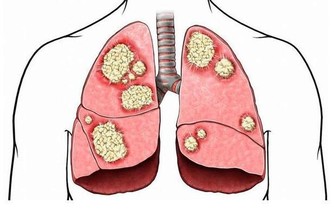

1.杵狀指

當你身體的含氧量太低,就可能會出現杵狀指。

指甲的底部和周邊呈現隆起的曲線。

這是心血管疾病或肺部腫瘤的指標。